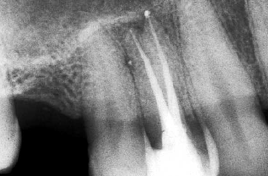

4- Grado de deterioro de la corona clínica por exposición a caries o trauma

Grandes obturaciones cercanas a la cámara pulpar,  en la mayoría de las veces es directamente proporcional al grado de calcificación de la cámara y de los conductos radiculares. Ver primer imagen derecha

La falta de la corona clínica puede ser causa de perforaciones accidentales. Ver segunda imagen derecha

La utilización sistemática de la radiografía periapical pre-operatoria evitaría estos accidentes que suelen ser comunes durante la práctica clínica.